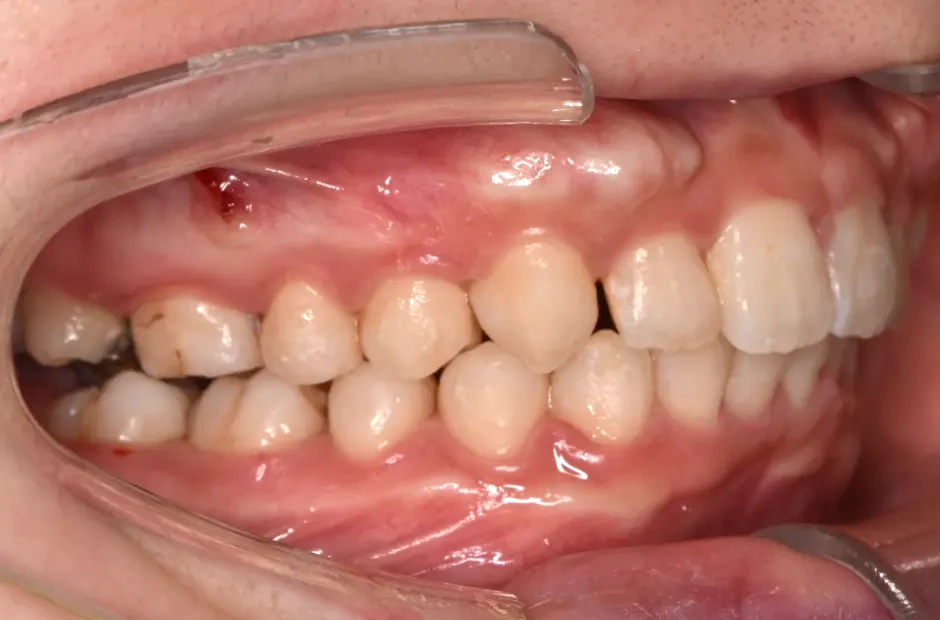

叢生

| 診断名・主訴 | 叢生 |

|---|---|

| 年齢・性別 | 43歳・女性 |

| 治療期間・回数 | 2年7か月 27回 |

| 治療に用いた主な装置 | 舌側矯正 |

| 抜歯部位 | 両顎4,4 |

| 治療費 | 100万円(税抜) |

| リスク・副作用 | 装置による違和感・疼痛・歯肉退縮・歯根吸収・虫歯のリスクなど |